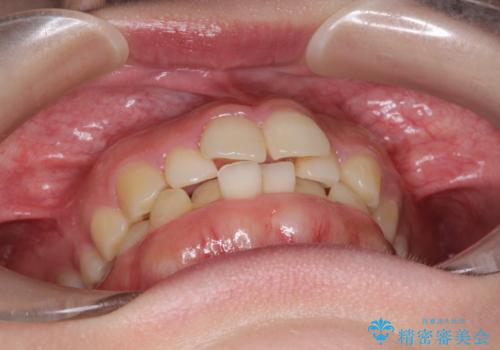

インビザラインでの前歯のガタガタの矯正

- 上下の前歯のがたつきを主訴に来院されました。

歯と歯の間をわずかに削りスペースを作り、インビザラインにて矯正治療を行うこととしました。

使用時間を守っていただけたので、スムーズに矯正を終了することができました。